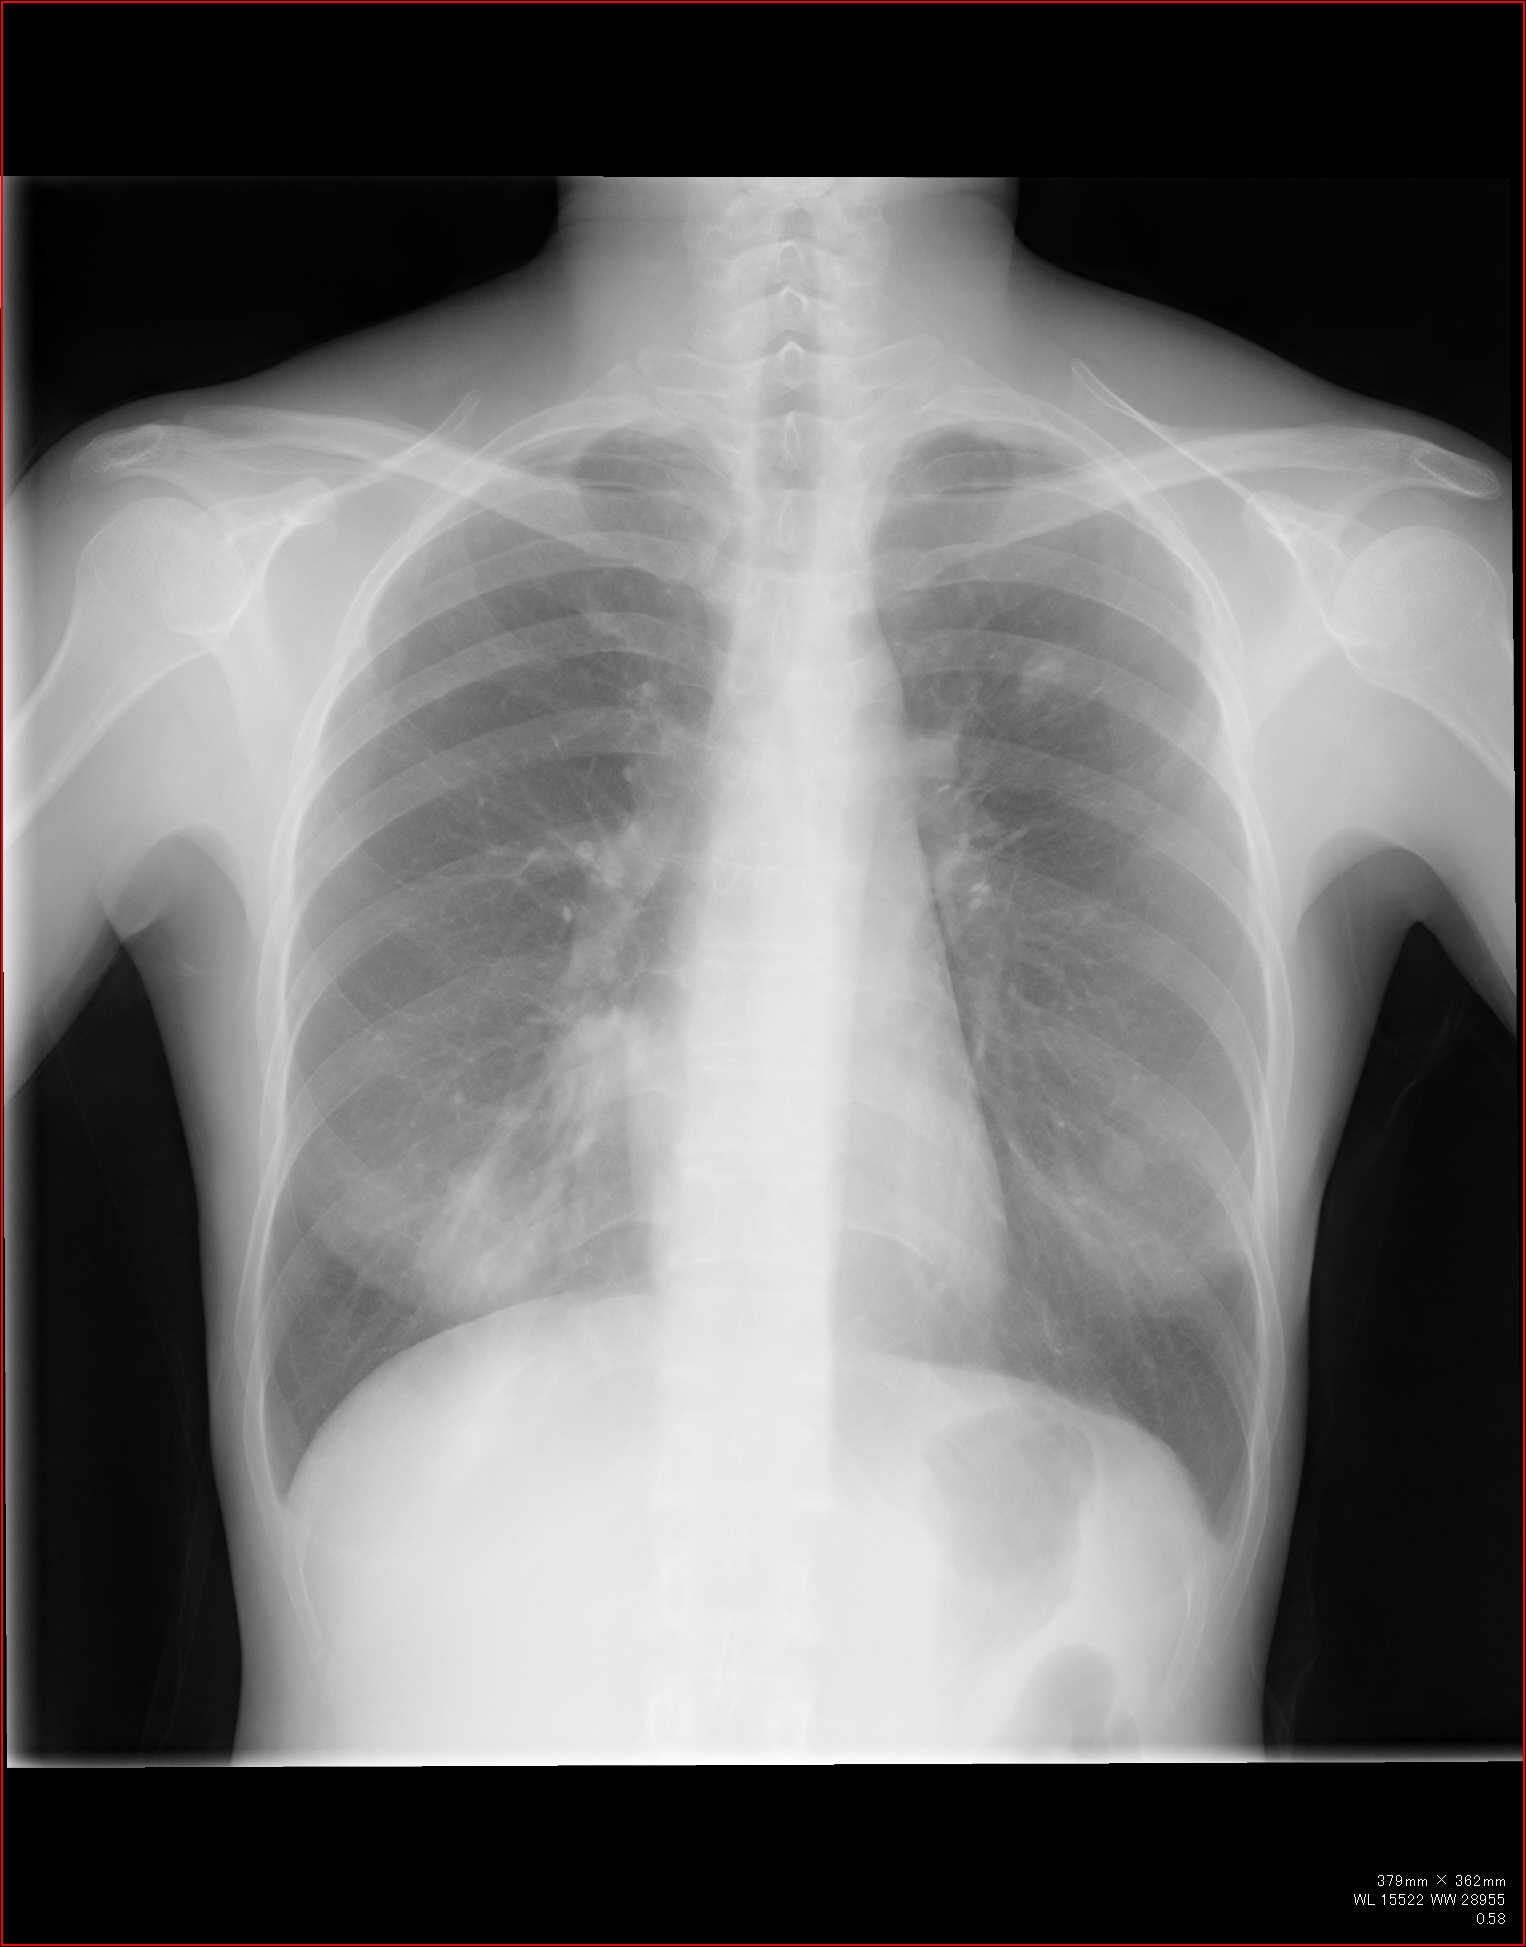

CT全盛の昨今、胸部レントゲン写真の意義は少なく見積もられがちではありますが…。

例えば診療所であったりして、CTはすぐに撮れない、という環境もあるわけです。

また、CTにも弱点があります。

例えば肺の大きさ。

volume

lossや反対に過膨張などの所見は、圧倒的に胸部正面写真がわかりやすいですね。

というわけで、

胸部レントゲン写真で、ここまでわかるか!というところを何回かに分けて、見て参りましょう。

胸部レントゲンの見方、系統的な見方はポリクリやアドバンスでかなり繰り返していますので改めては書きませんが、大事なポイントをおさらいしておきましょう。

@骨軟部影の所見を見逃さない

以前にあったような所見にも注意します。本当に多くの情報が骨軟部影に隠されています。